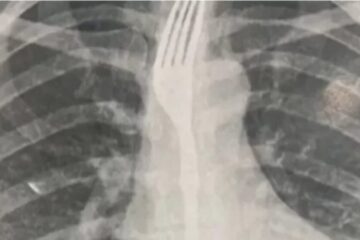

Jefferson foi socorrido e levado ao Hospital Regional, onde passou por procedimento cirúrgico, mas não resistiu.